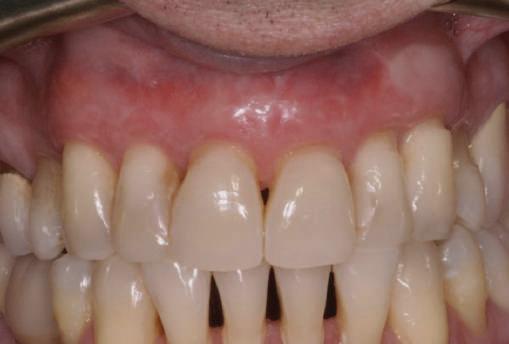

Alt caz (1) Figurile

4. După osteointegrarea implantului 2.4., s-a observat recesia în etapa de amprentare a implantului 2.5.; s-a decis reprepararea marginilor bontului individualizat CAD/CAM 2.4. Înainte de preparare s-a aplicat şnur de retracţie pentru a evita lezarea ţesutului şi a îmbunătăţi vizibilitatea dintelui 2.3. şi a marginii bontului implantar individualizat. Aşa cum era de aşteptat, recesia a fost mai mare de-a lungul versantului distal al bontului 2.4. adiacent locului de extracţie vindecat/cu implantul mai nou.

5. Bontul individualizat aplicat (2.5.) cu bontul repreparat anterior (2.4.). Nu a survenit recesie nouă de o perioadă de peste 3 ani.